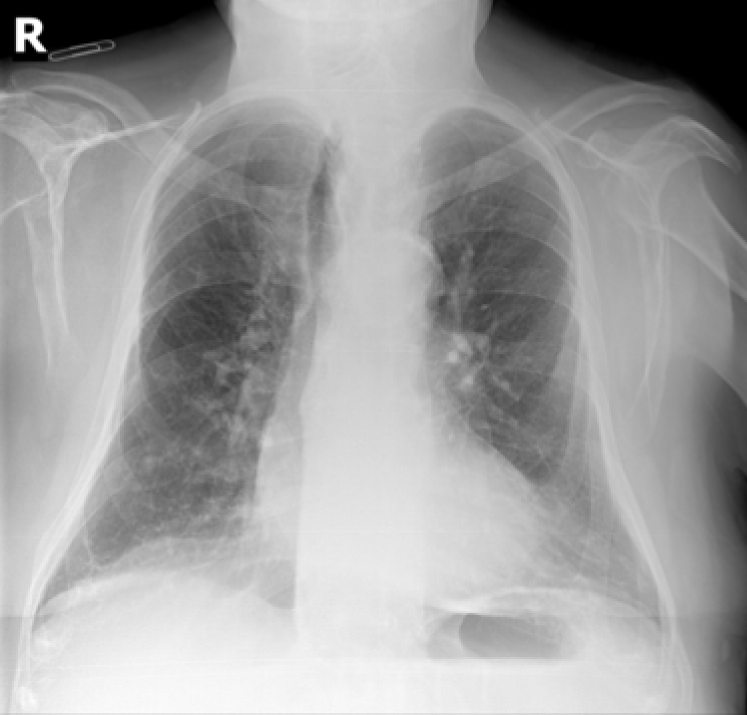

Refer to caption

(a) P-A

(b) Lateral

(c) Lordotic

(d) A-P supine

(e) A-P

(f) P-A

(g) Lateral

(h) Lordotic

(i) A-P supine

(j) A-P

Figure 2: Common chest x-ray projections.

The projection information is highly relevant for diagnosis. For example, AP views, which are commonly used in pediatric patients, show an enlarged heart silhouette (Fig. 2(j)) that should not be interpreted as cardiomegaly, but merely the expected large-depth ratio of reversed organ observation (Fig. 3). Another illustrative example is the distinct pattern that pleural effusions have in the standing position (Fig. 4(a)), in which a typical meniscus sign is commonly found as opposed to decubit projections (Fig. 4(b)). Given that the number of different projections is unbalanced (for instance, PA followed by lateral projections typically comprise the majority of chest x-rays), there is the risk that none of the other projections will have sufficient instances with which to train models capable of discriminating pathological from non-pathological patterns in the context of the projection.

There are particular radiological landmarks that differentiate projections, which radiologists are trained to identify. For instance, in the case of PA projections, these landmarks are the presence of air in the gastric chamber and the scapulae projected outside the lung fields. Although these features can be learned, models trained in unbalanced datasets with a poor representation for different projections may not have sufficient instances to properly learn those patterns. An illustrative example is when the heart enlargement in AP projections is attributable only to the effect of the projection, while the trained model erroneously predicts cardiomegaly.